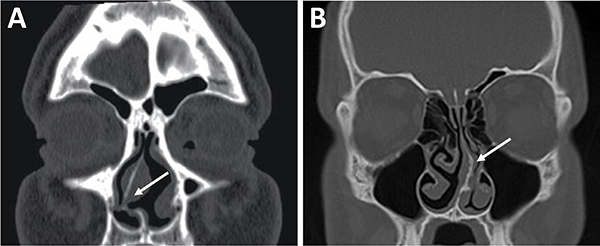

La evaluación del septum nasal podrá mostrar si presenta desviación o prominencias óseas que puedan dificultar el abordaje como también el tallado de un colgajo nasoseptal del lado elegido (fig. 9).[28] En caso de desvío septal se puede realizar septoplastia selectiva de la región desviada para logar un abordaje adecuado .

En referencia a las variantes turbinales se debe considerar la presencia de hipertrofia turbinal inferior y de cornetes medios bullosos (fig. 10). Ante la hipertrofia turbinal inferior será necesario realizar buena vasoconstricción preoperatoria asociada a luxofractura y lateralización para lograr un abordaje adecuado si es que no se asocia un tratamiento para la insuficiencia ventilatoria. Los cornetes medios bullosos representan una variante hipertrófica con neumatización de los mismos, los cuales podrán resecarse parcial o totalmente para lograr el correcto abordaje.

Figura 9: Desvío septal severo en TC cortes coronales. A) Inferior a fosa nasal derecha; B) Medio a fosa nasal izquierda.

Figura 10: Variantes turbinales en TC cortes coronales. A) Hipertrofia turbinal inferior (asteriscos blancos); B) Cornetes medios bullosos (asteriscos blancos) y desvío septal-espolón (flecha blanca).